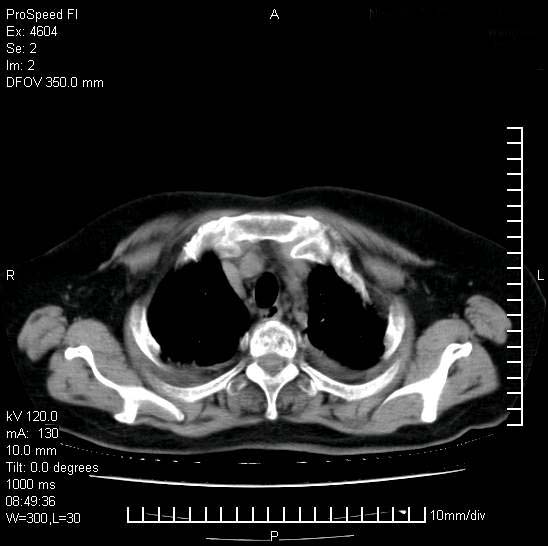

十几年前曾患肺结核,一周前突咳血约100ml,中性粒细胞稍高,诊断两上肺陈旧结核,下肺炎症,给予抗炎治疗,近几日晚上高热,39度,仍咳少量血,4天前ct及今天ct上传。

今天ct

短短几天内,病变范围明显增多扩大,以左侧明显,而且双侧出现胸水,还是考虑感染.

短短几天内,病变范围明显增多扩大,以左侧明显,而且双侧出现胸水,我更多考虑左侧中心性肺癌并并阻塞性不张及肺炎,炎症变化也太快了!

无论是肿瘤还是炎症4天的时间都发展够快的,并且还在治疗中,如果说是左肺癌那么右肺的病变不好解释,本人更加倾向于炎症,左肺舌叶支气管被痰栓或血凝块堵塞,造成阻塞性肺炎。

1)两肺结核并感染。2)不排除左肺上叶中央型肺癌并阻塞性肺炎、肺不张可能;建议行纤支镜检查。3)右肺门及纵隔淋巴结肿大。4)双侧胸腔积液。

陈旧性肺结核及左下肺不张,咯血后肺部感染,双胸腔积液,高热可能与痰液引流不畅有关。